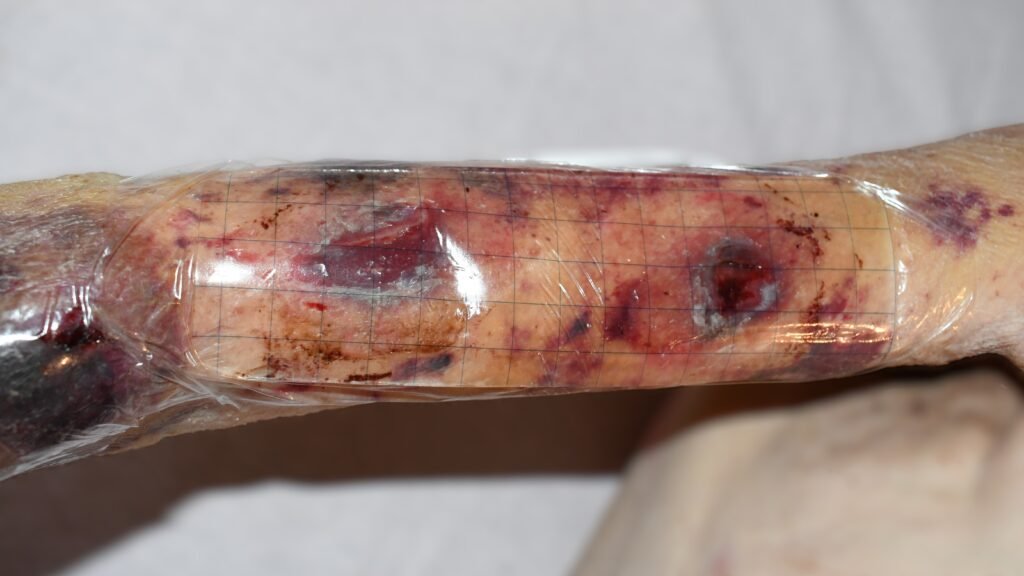

Hauptanwendungsgebiet: Wunden mit zerklüftetem Wundgrund. Durch Gelierung des Alginates wird eine Traumatisierung von Granulationsgewebe vermieden. Der alleinige Einsatz bei infizierten Wunden ist nicht möglich. Achtung beim Einsatz von Alginaten in Fistelgängen o.ä. Stark gelierende Alginate lassen sich nur schwerlich entfernen. Trockene Wunden und Nekrosen werden nicht mit Alginaten versorgt.

Bild 1: Tiefer Dekubitus am Gesäß

Bild 2: Wundheilungsstörung postoperativ am Bauchnabel